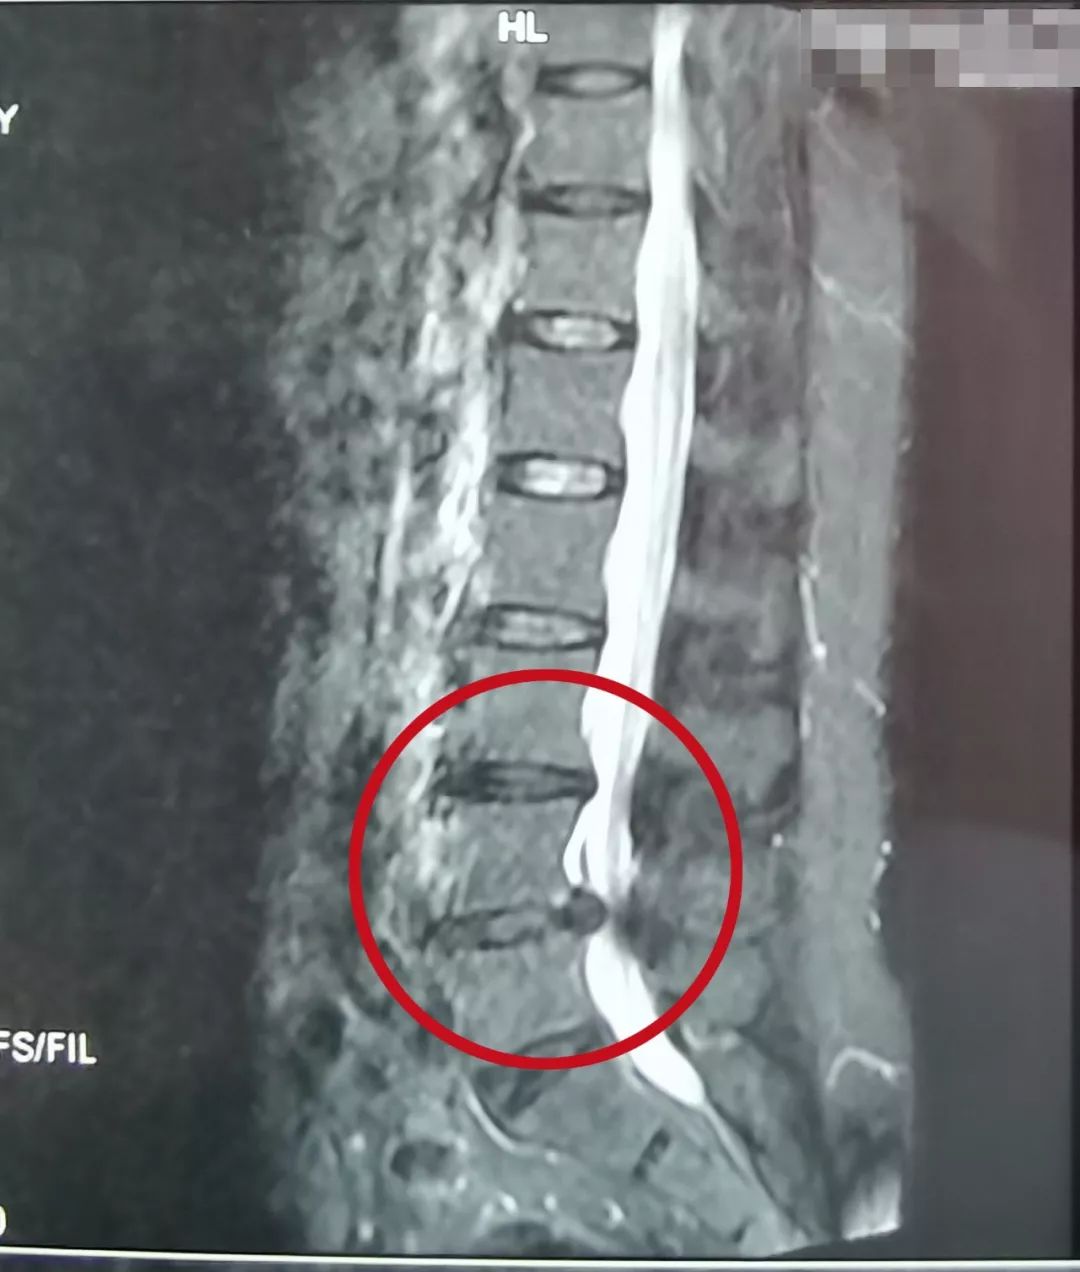

患者,女,63岁,主诉近期腰疼,双腿抽痛、麻木。之前在当地医院保守治疗1个月,效果不明显。

了解患者病情及影像学资料、仔细查体后,空军军医大学唐都医院骨科脊柱病区李晓祥博士诊断患者为腰椎间盘突出症、腰椎管狭窄症,并建议进行微创手术治疗。

像上面这样的患者出现症状影响生活,并且从影像学资料上看突出造成严重的腰椎管狭窄,已经压迫到神经,经过保守治疗后效果不好,这种情况就可以考虑手术治疗。